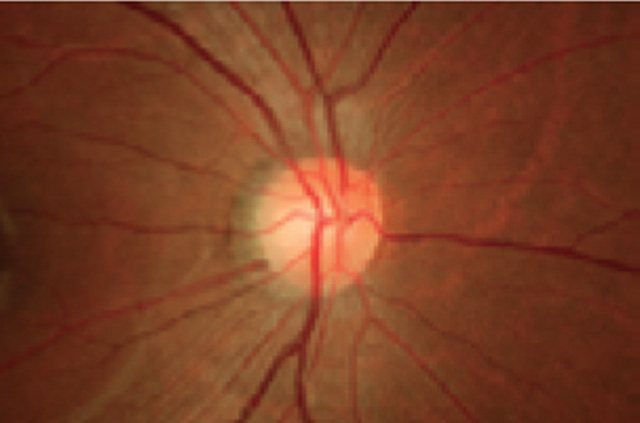

The Kowa nonmyd 7 is an easy-to-use fundus camera featuring 24 megapixel, high resolution photography.

Sharper, clearer images guarantee better clinical decisions.

The Nonmyd 7 is a high quality, simple to use digital retinal camera built with traditional Kowa reliability. Capture high levels of clinical detail with the sharp and clear images of the latest Nikon® digital camera. A choice of optical magnifications offers the standard 45° view or a 20° view for enhanced detail. A choice of fixation modes offers three standard positions while the optional external fixation target allows the user to choose the position on the retina. The industry standard USB interface connects to a desktop or laptop PC and the included Portable VK-2 digital imaging software lets you store, view, and compare your images with ease.